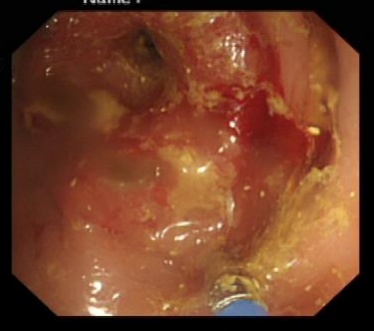

穿越“封锁线”:首先要将一根细长的导丝穿过肿瘤狭窄的缝隙。这需要极大的耐心和手感,患者肿瘤位置扭曲,肠道内粪便和血液堆积,视野极差,处于“看得见摸不着”的地方,陈华不断变换角度和位置,终于让导丝顺利通过。

架设“生命之桥”:在放置支架时,因肿瘤形态导致支架与肠壁形成了一个危险的30度夹角,难以越过狭窄段。此时若强行推进,极易导致肠道穿孔,后果不堪设想。

千钧一发之际,陈华沉着应对,通过反复、轻柔地推拉和调整,不断尝试最佳角度,如同在体内进行一场精密的“穿针引线”。最终,凭借丰富的经验和稳定的手法,支架被精准地放置到了预定位置,肠道瞬间被撑开,“生命通道”恢复了畅通!